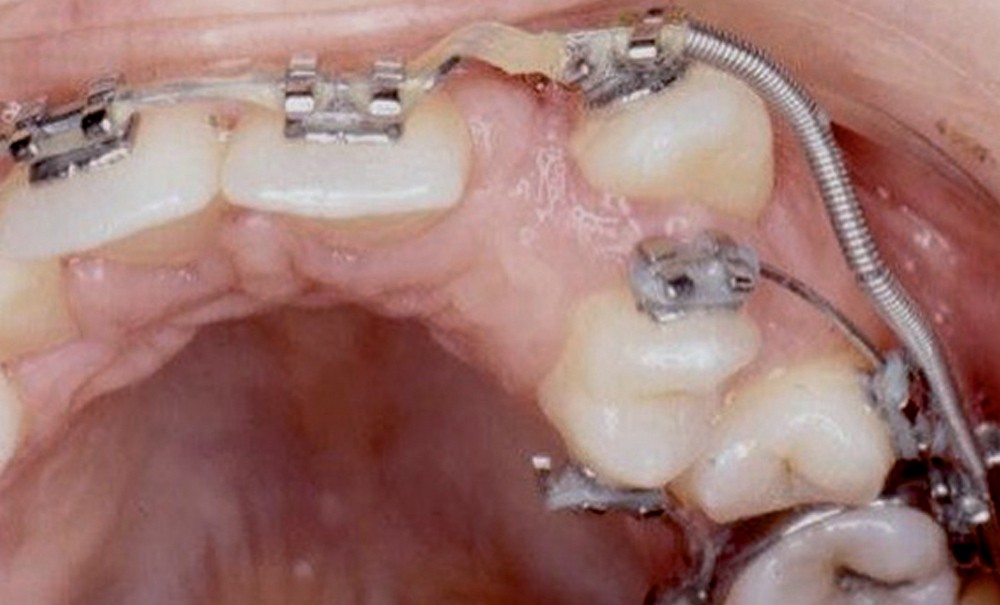

Avec Peretz, en 1998 [2], on distinguera les transpositions complètes, où couronnes et racines sont transposées, des transpositions incomplètes, où seule la couronne est transposée. Pour les transpositions complètes, on différenciera les transpositions complètes totales, où la dent transposée est dans la courbe d’arcade, des transpositions complètes partielles, où la dent transposée est vestibulaire par rapport à la courbe d’arcade.

La transposition la plus fréquente est la transposition canine/prémolaire maxillaire (à peu près 70 % des cas). La transposition canine/incisive latérale maxillaire représente pratiquement 20 % des cas ; elle peut le plus souvent être traitée orthodontiquement, dans la mesure où elle est presque toujours soit complète partielle, soit (le plus souvent) incomplète.

Ce sont les transpositions canines/prémolaires maxillaires que nous allons étudier.